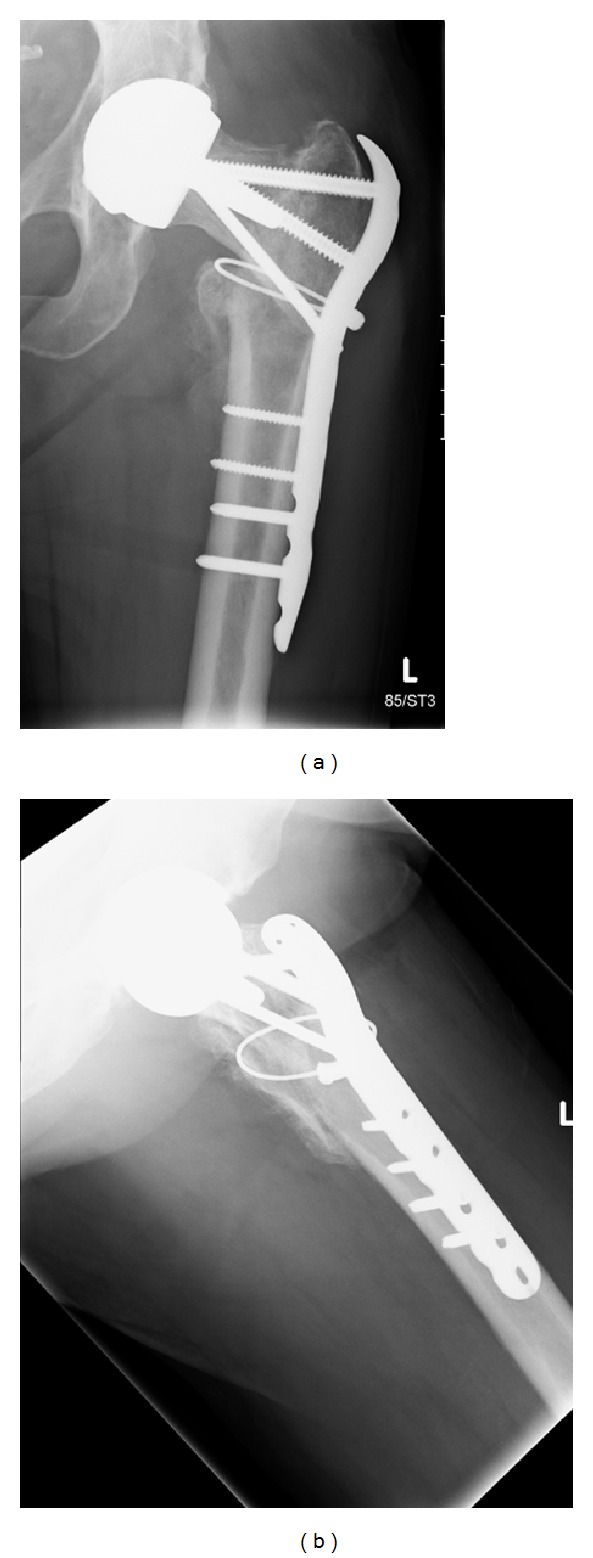

A 56-year-old lady presented to hospital after a fall onto her left hand side, after which she was unable to weight bear. On examination her leg was shortened, externally rotated, and neurovascularly intact. There was a history of previous bilateral Birmingham hip resurfacing (Smith & Nephew) with the left side five years prior to admission and the right side one year before. Other past medical history included, osteoarthritis affecting hands, hips, knees and spine, as well as hypertension and diet controlled type 2 DM. There had also been a recent history of increased alcohol consumption. A pelvic X-ray taken in 2007 demonstrated significant bilateral hip osteoarthritis. Figure 1 shows a radiograph from 2009 after her right hip resurfacing and prior to surgery on the left. Figure 2 demonstrates the injury sustained in early December 2012.

Figure 2.

(a) and (b), AP views. (c) Lateral view.